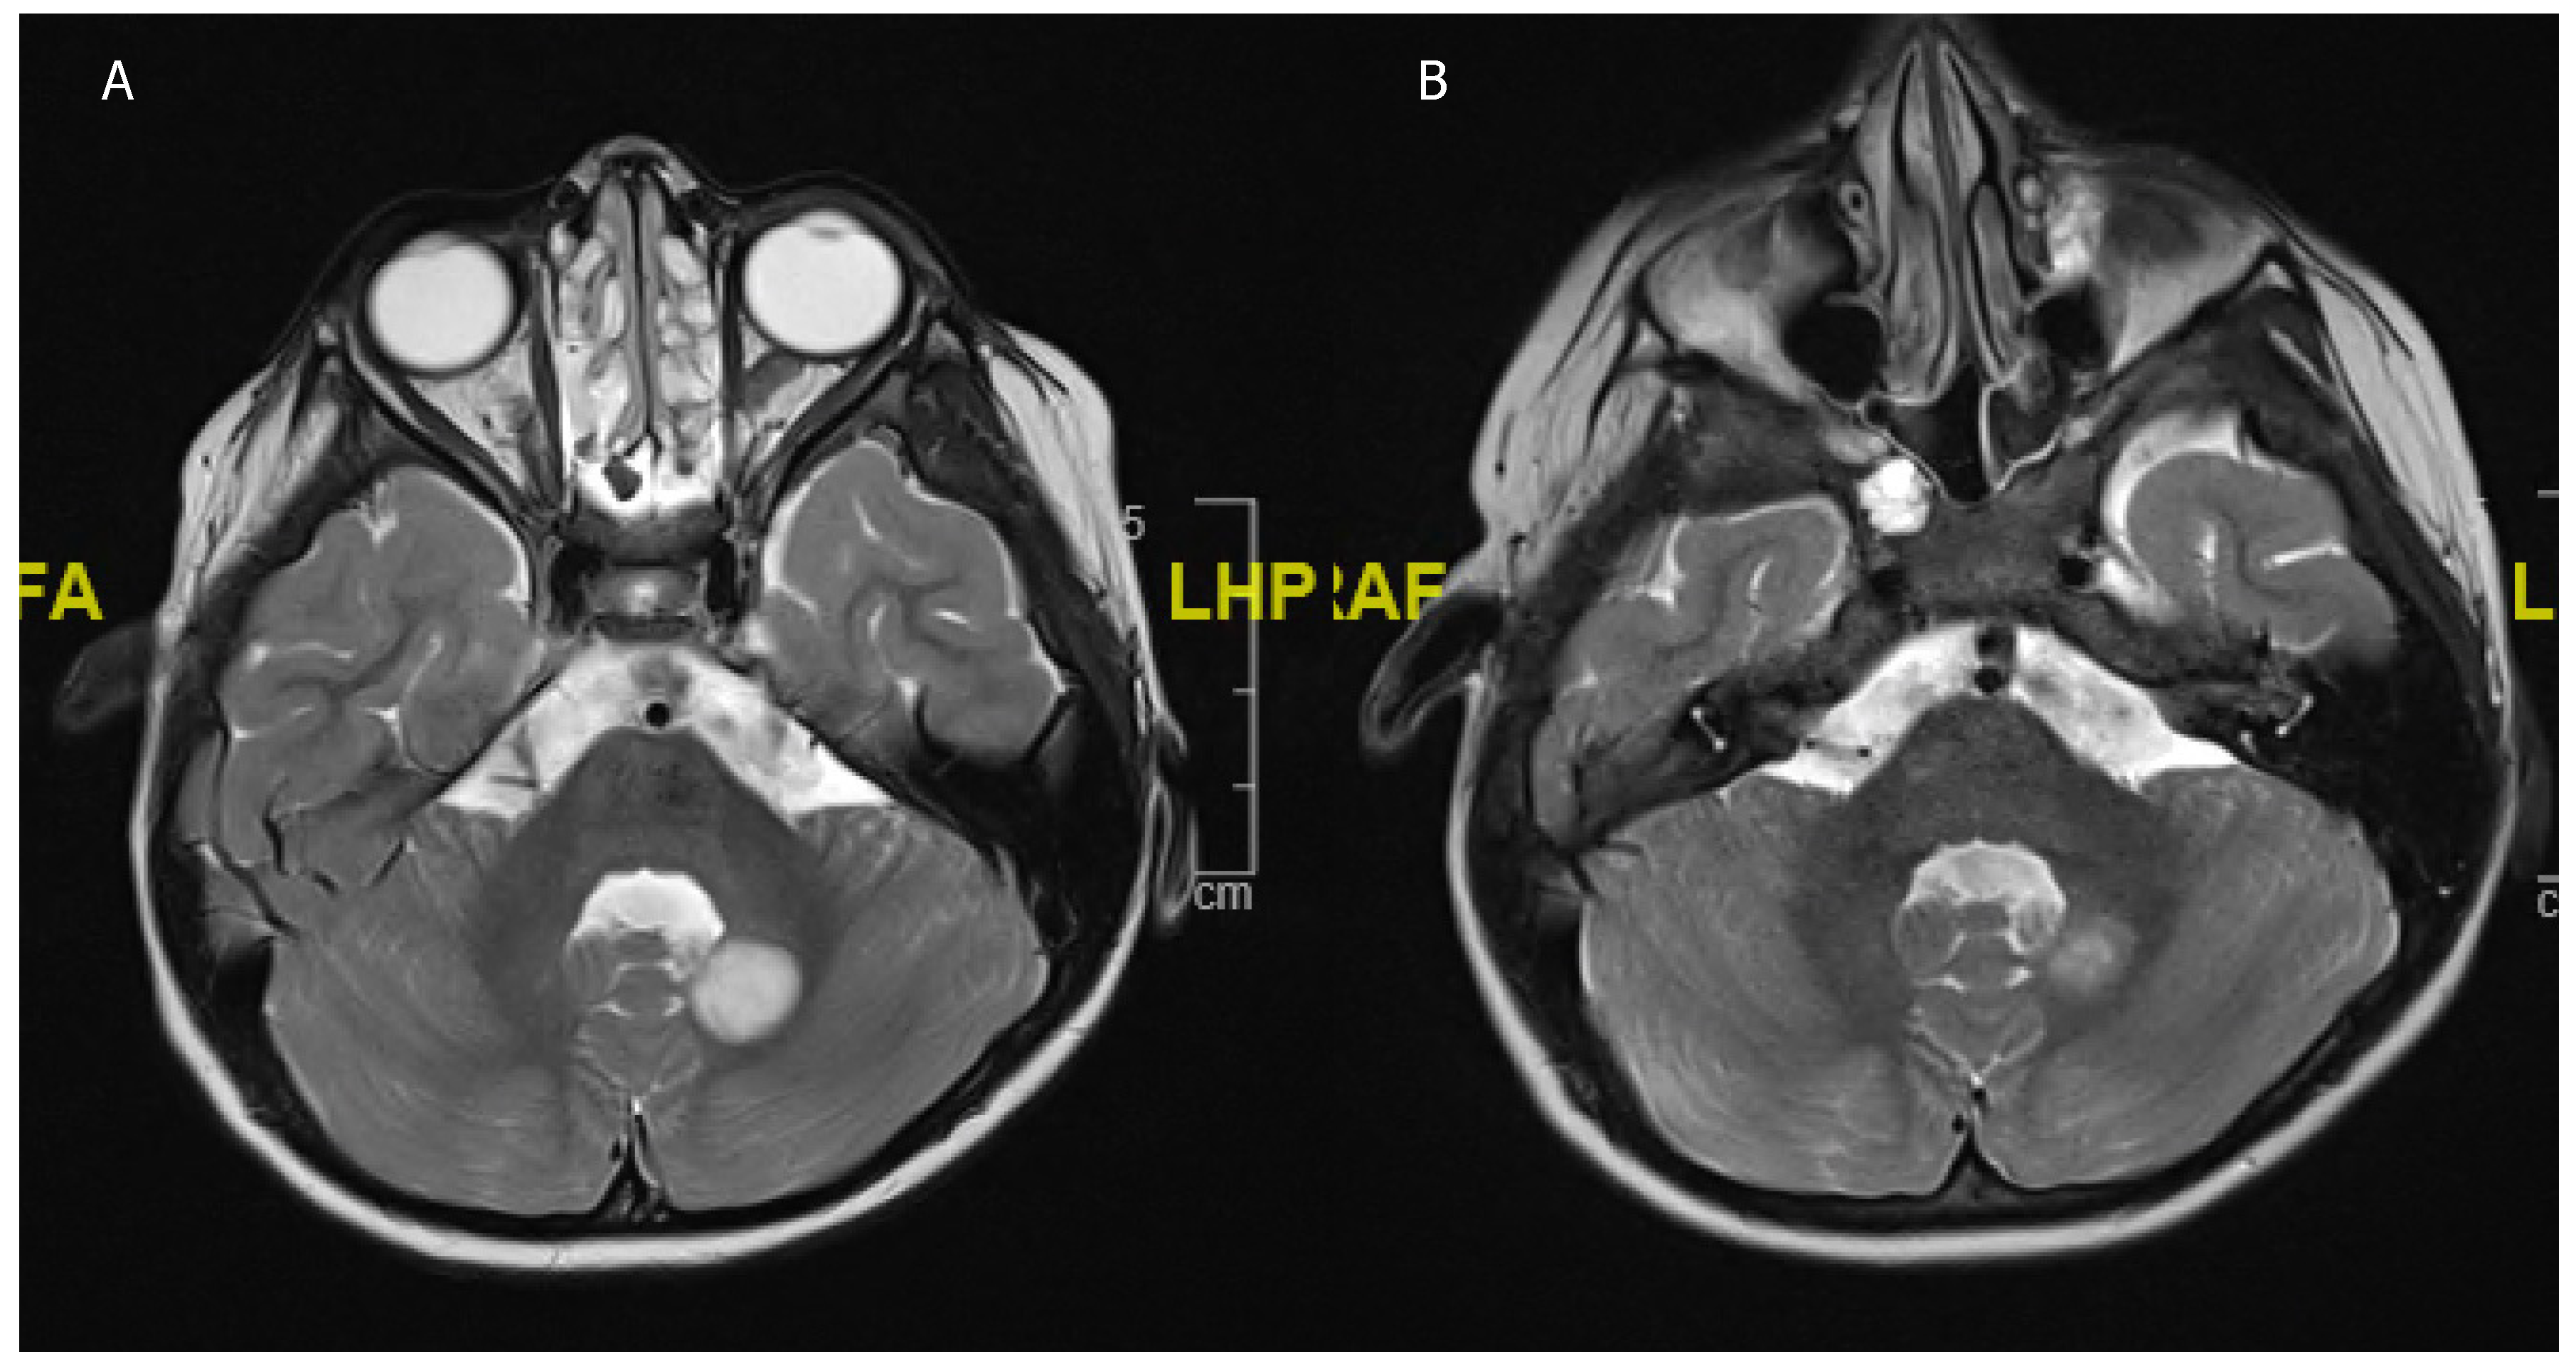

Figure 1. A 21-year-old male, presenting with a generalized seizure. (A) Flair hyperintense fronto-temporal tumor of 8.6 × 4.5 × 5 cm with central hypointensity suggestive of aLGG. (B) T1 hypointense tumor surrounded by the vessels of the sylvian fissure. (C) Postoperative imaging after awake fronto-temporal craniotomy and partial tumor resection due to language impairment intraoperatively.

2. Histology and Anatomical Location

In children, most LGGs are pilocytic astrocytoma (65%), followed by LGG not otherwise specified (NOS) in 21% of cases. Approximately, three quarters of all LGGs in children are WHO grade I [8]. In adults, it is the opposite, with over three quarters of aLGG being WHO grade II [6]. PLGGs occur in 60%, either in the supra- or in the infratentorial compartment, while aLGGs occur in 60% of cases supratentorially, with 80% in eloquent regions [6,18]. In children, certain tumor locations, such as the tectum or the dorsal brainstem, are pathognomonic for pLGG, specifically pilocytic astrocytoma (PA), and it is disputed whether these tumors even require a biopsy to confirm the diagnosis, since surgery around the brainstem has a rate of postoperative morbidity of up to 30% [9,19]. Therefore, if hydrocephalus is apparent, endoscopic biopsy is obtained simultaneously to an endoscopic third ventriculostomy (ETV), which is indicated in order to treat the aqueduct stenosis caused by the tumor [20,21,22]. A classic location for aLGG is the insular region, which presents specific challenges (Figure 1). These tumors are very closely located to the middle cerebral artery and are surrounded by its branching vessels in a highly eloquent region, which often involves speech, motor, and limbic functions [23]. Approximately 6% of all pLGGs show dissemination either in other parts of the brain or the spine, while in adults dissemination is only observed in high grade gliomas [24,25]. However, the benefit of a whole neuroaxis scan at diagnosis and follow-up is still controversially discussed in pLGG [26].